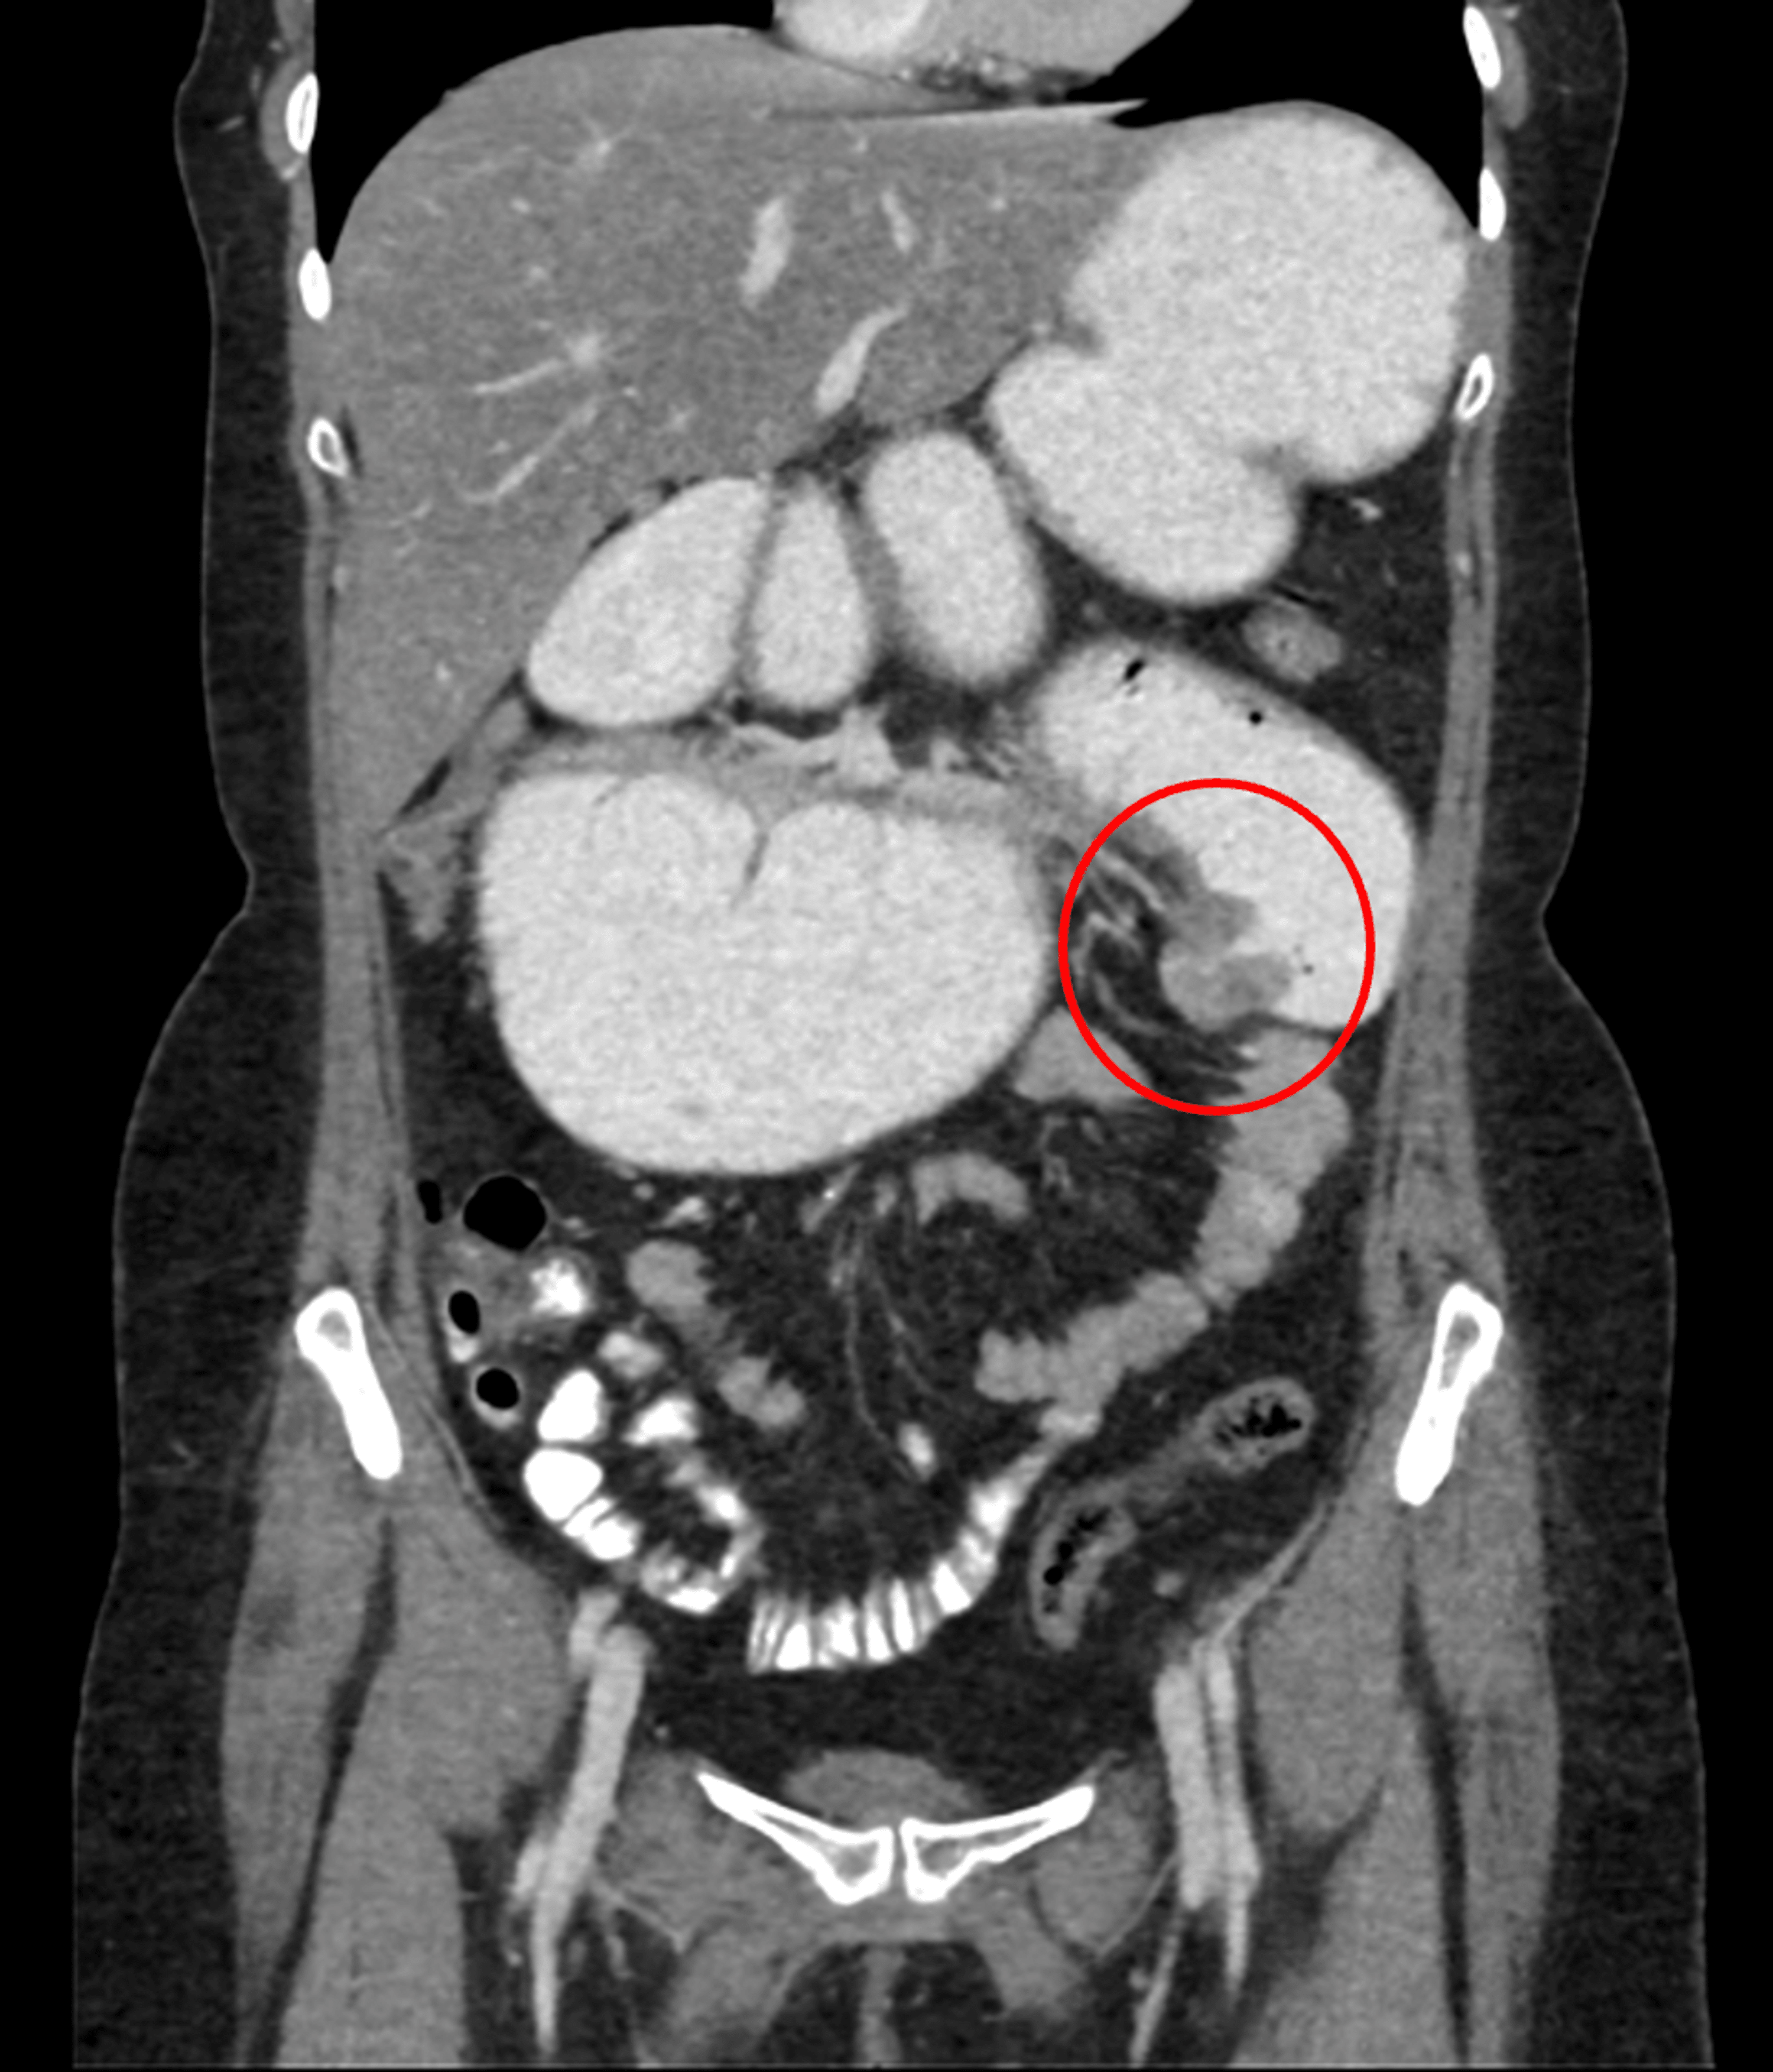

Concertina Effect Jejunum . It allows back diffusion through leaky. jejunal mucosa is more permeable to water, sodium and chloride than ileal mucosa. the concertina effect is the progressive shortening of pr interval with corresponding widening of the qrs. • the jejunum is characterized by its valvulae conniventes that completely pass across the width of the bowel and are. the accordion sign (also known as the concertina sign) on ct scans is defined as the alternation of broad bands. the accordion sign (also known as concertina sign) is seen on ct of the abdomen and refers to the similarity. adenocarcinoma of the small bowel tends to occur proximally (duodenum. small bowel transit time was unaffected by infusion of nutrients into the colon or jejunum, although jejunal colonic infusion.

the accordion sign (also known as the concertina sign) on ct scans is defined as the alternation of broad bands. adenocarcinoma of the small bowel tends to occur proximally (duodenum. the concertina effect is the progressive shortening of pr interval with corresponding widening of the qrs. jejunal mucosa is more permeable to water, sodium and chloride than ileal mucosa. • the jejunum is characterized by its valvulae conniventes that completely pass across the width of the bowel and are. the accordion sign (also known as concertina sign) is seen on ct of the abdomen and refers to the similarity. It allows back diffusion through leaky. small bowel transit time was unaffected by infusion of nutrients into the colon or jejunum, although jejunal colonic infusion.

Jejunum Anatomy, histology, function, composition Kenhub Concertina Effect Jejunum the accordion sign (also known as concertina sign) is seen on ct of the abdomen and refers to the similarity. small bowel transit time was unaffected by infusion of nutrients into the colon or jejunum, although jejunal colonic infusion. the accordion sign (also known as the concertina sign) on ct scans is defined as the alternation of. Concertina Effect Jejunum.